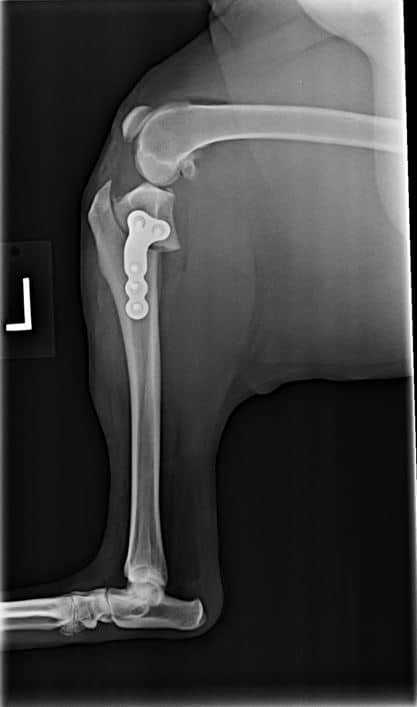

After TPLO